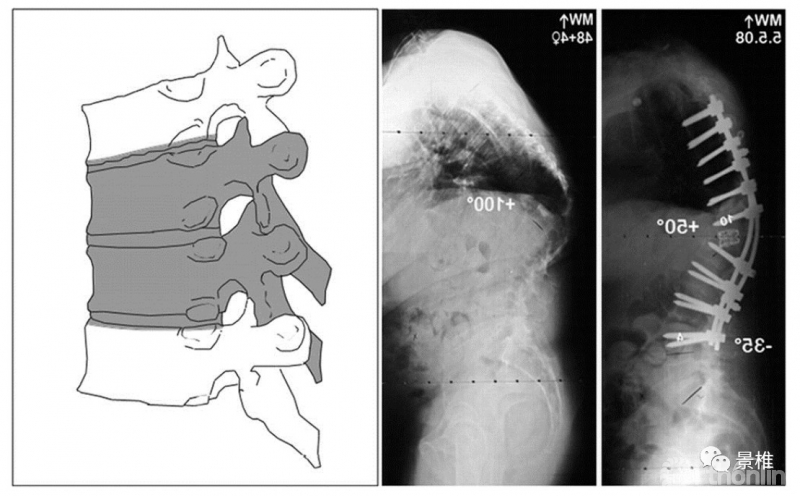

6级 VCRs

6级,多个椎体的5级截骨。

各级截骨矫形度数简记:级数×10º